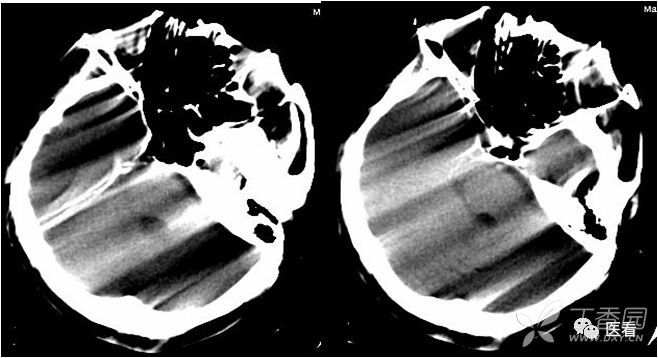

8 受检者自身结构与设备双重原因

亨氏暗区

颅底(致密)骨产生的横行或放射状伪影,与设备性能也有关系

下图为16拍MSCT,伪影较轻。

此图为双排螺旋 CT图像, 伪影较16层及以上MSCT显著的多。